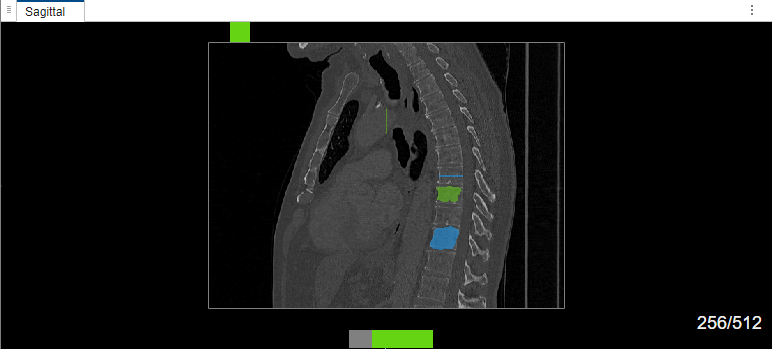

Label Multiple Objects in Image

Select label Type1. Draw a bounding box around the object to segment in the sagittal plane of the volume. The MedSAM algorithm extracts the embeddings of the image and segments the object in the bounding box. Then, select label Type2. Draw a bounding box around the object to segment in the sagittal plane of the volume. Because this is the second object segmented in the same image during the same labeling session, the MedSAM algorithm does not extracts the embeddings of the image again. The algorithm directly segments the object in the bounding box.